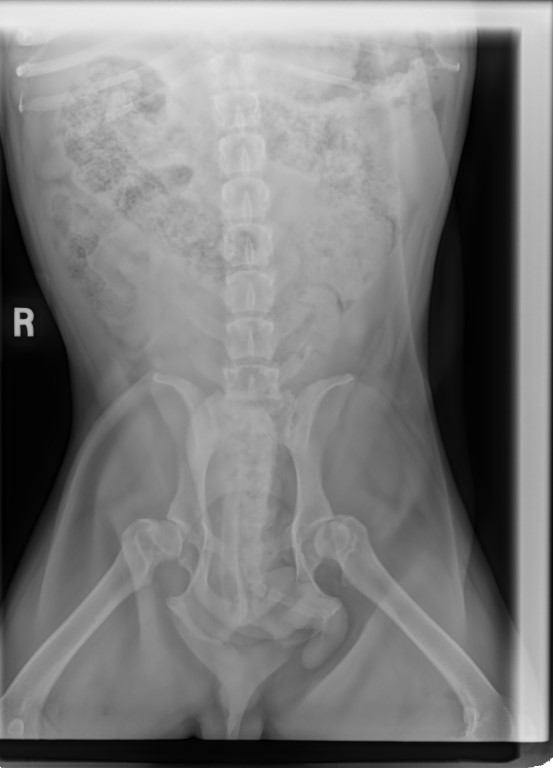

I took him to KAH as I wanted to get an updated weight on him for he had dropped down to 19 kgs and, he was back up to 20 kgs, so giving him the extra 1.5 cups daily as his body fought these infections etc., has helped. He was 20.2 kgs the day he went to his temp foster home.

I cannot stress enough about how I want to see him between 19.8 kgs and 20.5 kgs. He is not to become obese and, of course, we do not want him skinny. Lean and healthy! He is so fit and, looking like a Bulldog should, not what people' 'think' bulldogs should look like – rotund with stomachs protuding.